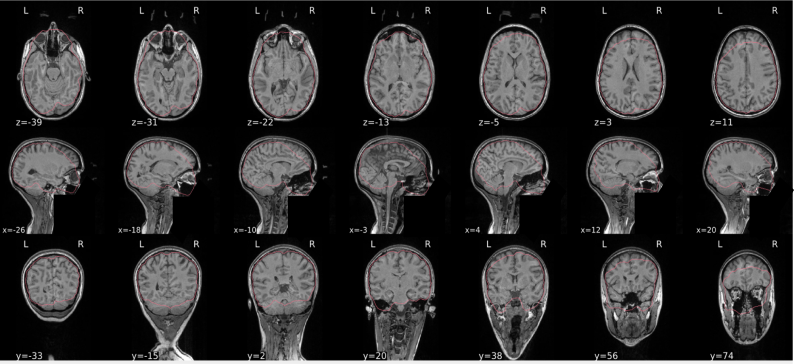

Example of a bad subject

- There are skull stripping errors, such as portions of the brain missing, or too much of the skull retained

- NOTE: check all the images (slices) in the report. If only one image (slice) looks problematic, it is possible that the subject is okay and it is just a visual issue in that particular screenshot

Summary

| Good | Bad |

|---|---|

| The brain is fully inside the red line | Structures like the cranium or the eyes are inside the red line |

| No important brain structures are outside of the red line red line follows the natural outline of the brain | Important brain structures are missing inside of the red line |

-> if only one slice is problematic, it could be an issue related to the visual depiction of the data instead of an issue related to the test subject